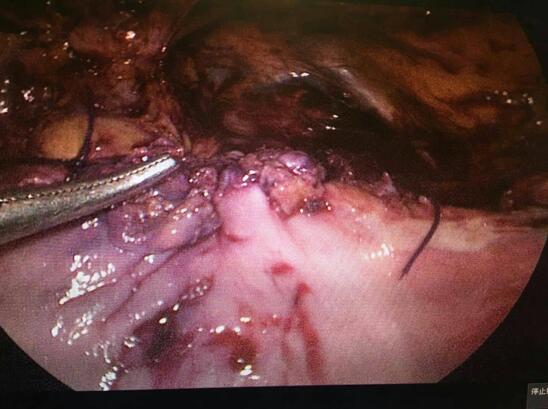

• 多学科合作,微创切“瘤”——瑞康妇科在临时起搏器的保护下成功实施一例心脏III度房室传导阻滞患者的腹腔镜巨大宫颈肌瘤剔除术

多学科合作,微创切“瘤”——瑞康妇科在临时起搏器的保护...

子宫肌瘤是女性生殖器官中最常见的良性肿瘤。子宫肌瘤的症状取决于肌瘤的部位、大小、数目和并发症。子宫肌瘤的处理因人而异,根据年龄、有无症...

• 微创切“瘤”,精益求精

微创切“瘤”,精益求精

子宫肌瘤是女性生殖器官中最常见的良性肿瘤。子宫肌瘤的症状取决于肌瘤的部位、大小、数目和并发症。随着体检的普及,一部分的肌瘤患者无症状...